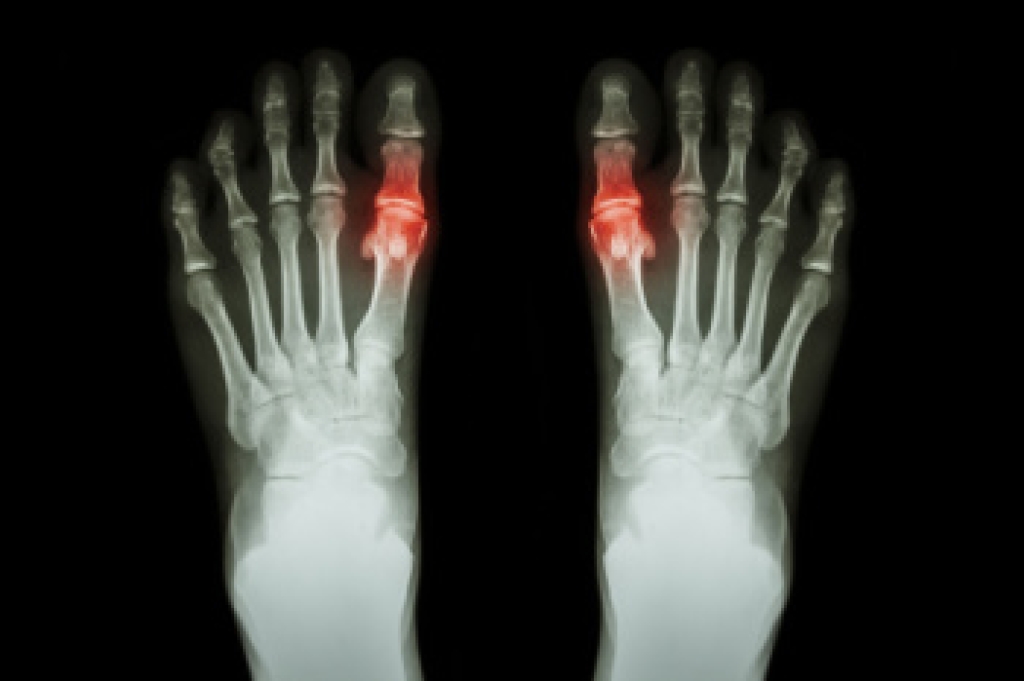

Diabetic foot wounds develop from a combination of nerve and blood vessel damage caused by prolonged high blood sugar levels. Nerve damage, or neuropathy, reduces sensation in the feet, making it difficult to notice minor injuries like cuts or blisters. Also, poor blood flow, resulting from damaged blood vessels, slows healing and increases the risk of infections. Common triggers for diabetic foot wounds include wearing ill-fitting shoes, foot deformities like bunions or hammer toes, and excessive callus formation. Early symptoms may include dry or warm skin, tingling, and numbness. The appearance of poorly healing sores, particularly on the soles, toes, or heels are other factors. In advanced cases, such wounds can deepen, become infected, or result in tissue death and possible limb loss. A podiatrist can assess nerve and blood flow issues, treat wounds, and recommend preventive measures like proper footwear and regular foot examinations. If you have foot problems related to diabetes, it is suggested that you schedule an appointment with a podiatrist for ongoing foot care.